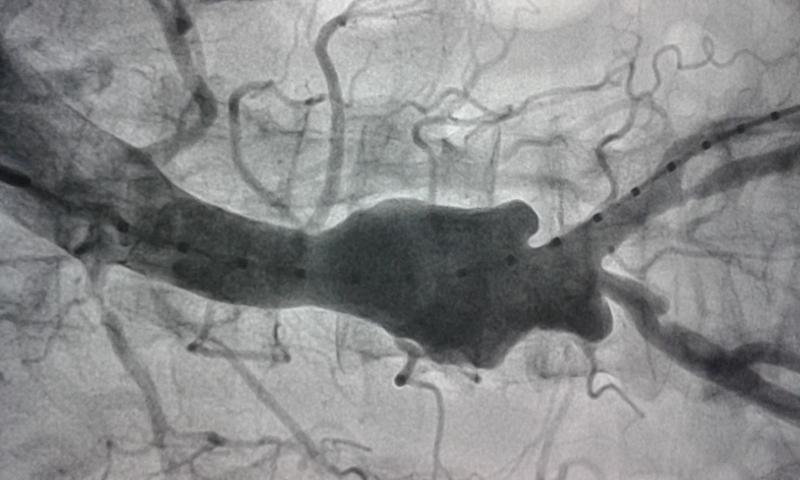

Picture of the infraabdominal aortic aneurysm repair using a bifurcation graft to give proper flow to both the iliac arteries is shown below

Before and after repair

The above is the aneurysm and below is the scan after repair